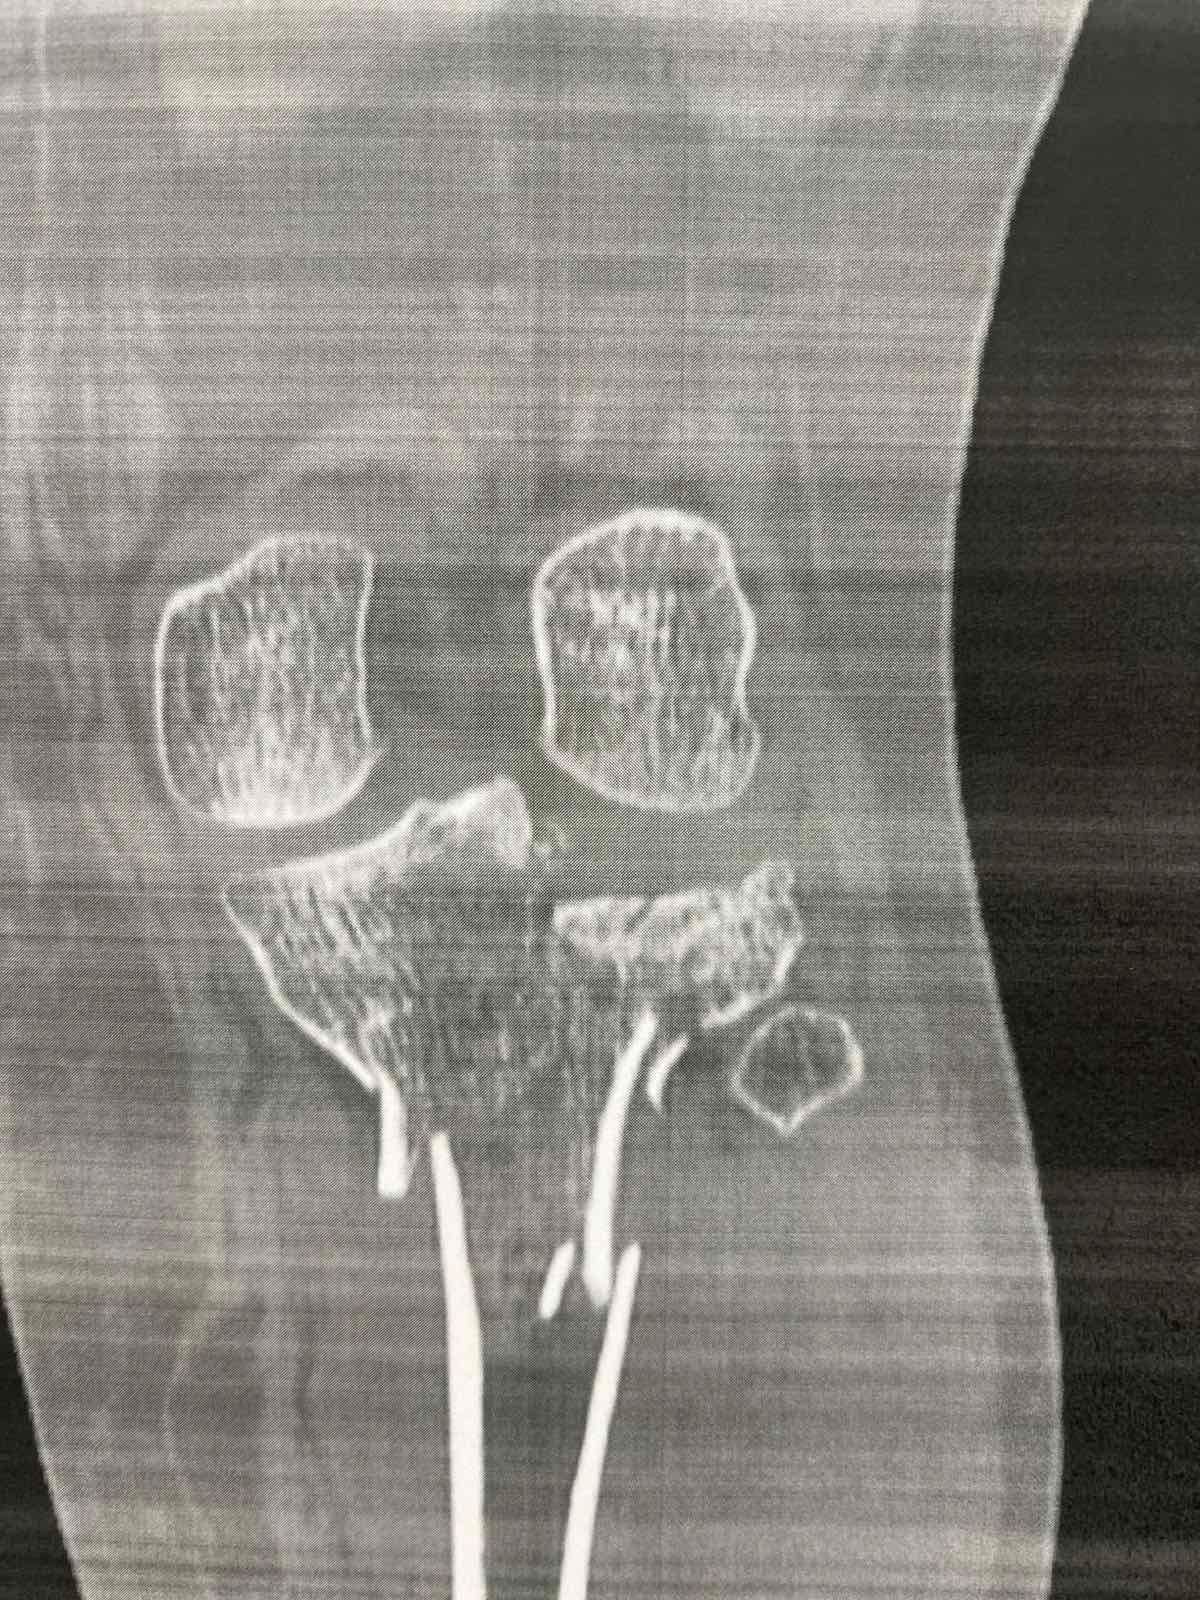

Πριν το χειρουργείο (απεικονίσεις τραυματισμού)

Ο Schatzker τύπος VI είναι από τις πιο βαριές κακώσεις: πρόκειται για κάταγμα του πλατώ με μεταφυσιο-διαφυσιακή ασυνέχεια(δηλαδή «διαχωρισμό» της μεταφύσεως από τη διάφυση), συχνά μετά από υψηλής ενέργειας τραυματισμό. Τέτοιες κακώσεις μπορεί να συνοδεύονται από σημαντικό οίδημα/βλάβες μαλακών μορίων και απαιτούν ιδιαίτερη προσοχή στον χρόνο και στον τρόπο αποκατάστασης.

Τα κατάγματα του κνημιαίου πλατώ αφορούν την άνω επιφάνεια της κνήμης που συμμετέχει στην άρθρωση του γόνατος. Η ταξινόμηση Schatzker χρησιμοποιείται ευρέως για να περιγράψει το μοτίβο του κατάγματος.